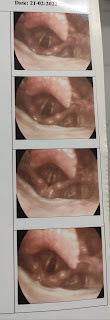

DIRECT LARYNGOSCOPY :